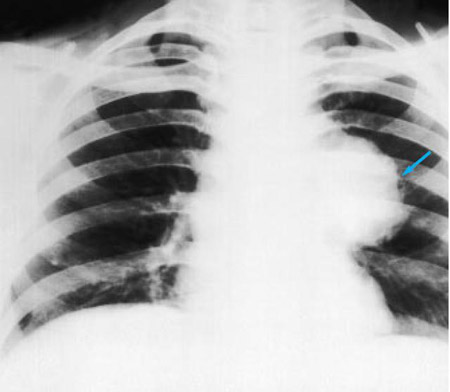

Chest x-ray

A chest x-ray should be obtained early in the evaluation of chronic cough.[38] Although it is not diagnostic of the most common causes, findings may quickly divert the evaluation to causes of greater gravity, such as structural lung diseases. These include lung cancer, pulmonary fibrosis, tuberculosis, bronchiectasis, pneumonia, aspiration, and sarcoidosis.[Figure caption and citation for the preceding image starts]: Chest x-ray showing hyperinflation in a patient with COPD. The hyperinflation is caused by the emphysema component of COPD, rather than the chronic bronchitis that underlies symptoms of coughFrom the personal collection of Dr M. A. Sharifabadand, SUNY at Stony Brook School of Medicine, Department of Pulmonary and Critical Care Medicine, Mineola, New York and Dr J. P. Parsons, The Ohio State University Medical Center, Columbus; used with permission [Citation ends].com.bmj.content.model.assessment.Caption@65a65855[Figure caption and citation for the preceding image starts]: Chest x-ray showing multiple miliary lung metastases (arrows). The primary tumour was a thyroid carcinomaE. Dick, Student BMJ. 2001;9:10-12 [Citation ends].com.bmj.content.model.assessment.Caption@25657fee[Figure caption and citation for the preceding image starts]: Chest x-ray showing left hilar carcinoma (arrow)From: E. Dick, Student BMJ. 2000;8:358-360 [Citation ends].com.bmj.content.model.assessment.Caption@567b9fef[Figure caption and citation for the preceding image starts]: Chest x-ray showing a cavitating right hilar carcinoma (arrow)E. Dick, Student BMJ. 2001;9:10-12 [Citation ends].com.bmj.content.model.assessment.Caption@3d6fa55[Figure caption and citation for the preceding image starts]: Chest x-ray in a patient with bronchogenic carcinoma showing a left-sided pleural effusionFrom: R. Thakkar, Student BMJ. 2001;9:458 [Citation ends].com.bmj.content.model.assessment.Caption@5b46acec[Figure caption and citation for the preceding image starts]: Chest x-ray showing interstitial fibrosis in a patient with amiodarone pulmonary toxicityFrom the personal collection of Dr A. Pataka and Professor P. Argyropoulou, Aristotle University, Thessaloniki, Greece; used with permission [Citation ends].com.bmj.content.model.assessment.Caption@2c3c94b0[Figure caption and citation for the preceding image starts]: Chest x-ray showing pulmonary tuberculosis with cavitationFrom the personal collection of Dr M. Narita, Department of Pulmonary and Critical Care Medicine, University of Washington [Citation ends].com.bmj.content.model.assessment.Caption@3dd7f84b[Figure caption and citation for the preceding image starts]: Chest x-ray showing multiple discrete nodules throughout both lungs (one of which is circled) in a patient with miliary tuberculosisE. Dick, Student BMJ. 2001;9:10-12 [Citation ends].com.bmj.content.model.assessment.Caption@23fa6365[Figure caption and citation for the preceding image starts]: Chest x-ray with lack of normal tapering producing a tram line in a patient with bronchiectasisFrom the personal collection of Dr S.M. Bhorade, University of Chicago Medical Center; used with permission [Citation ends].com.bmj.content.model.assessment.Caption@36b415f2[Figure caption and citation for the preceding image starts]: Chest x-ray with dilated and thickened airways in a patient with bronchiectasisFrom the personal collection of Dr S.M. Bhorade, University of Chicago Medical Center; used with permission [Citation ends].com.bmj.content.model.assessment.Caption@78e208fa[Figure caption and citation for the preceding image starts]: Chest x-ray showing increased opacification of the right perihilar region and superior segment of the right lower and upper lobes consistent with worsening aspiration pneumoniaFrom the personal collection of Dr R. Kanner, University of Utah School of Medicine [Citation ends].com.bmj.content.model.assessment.Caption@71be2c1f[Figure caption and citation for the preceding image starts]: Portable chest x-ray with bibasilar opacities, worse on the right than the left, in a patient with hospital-acquired pneumoniaFrom the personal collection of Dr F. W. Arnold, Division of Infectious Diseases, Department of Medicine, University of Louisville School of Medicine [Citation ends].com.bmj.content.model.assessment.Caption@2c704497[Figure caption and citation for the preceding image starts]: Chest x-ray showing early ill-defined opacities of the right upper lobe above the minor fissure consistent with early changes of aspiration pneumoniaFrom the personal collection of Dr R. Kanner, University of Utah School of Medicine [Citation ends].com.bmj.content.model.assessment.Caption@23fa54d0[Figure caption and citation for the preceding image starts]: A. Portable upright chest x-ray before aspiration; B. Chest x-ray 1 hour after aspiration, showing bilateral diffuse alveolar infiltrates, worse at the bases on the right sideFrom the personal collection of Dr S. Murgu and Dr H. Colt, University of California at Irvine Medical Center [Citation ends].com.bmj.content.model.assessment.Caption@7860be3a[Figure caption and citation for the preceding image starts]: Chest x-ray showing bilateral hilar adenopathy in a patient with sarcoidosisFrom the personal collection of Dr M.P. Muthiah, Division of Pulmonary and Critical Care and Sleep Medicine, University of Tennessee [Citation ends].com.bmj.content.model.assessment.Caption@31e94b4e